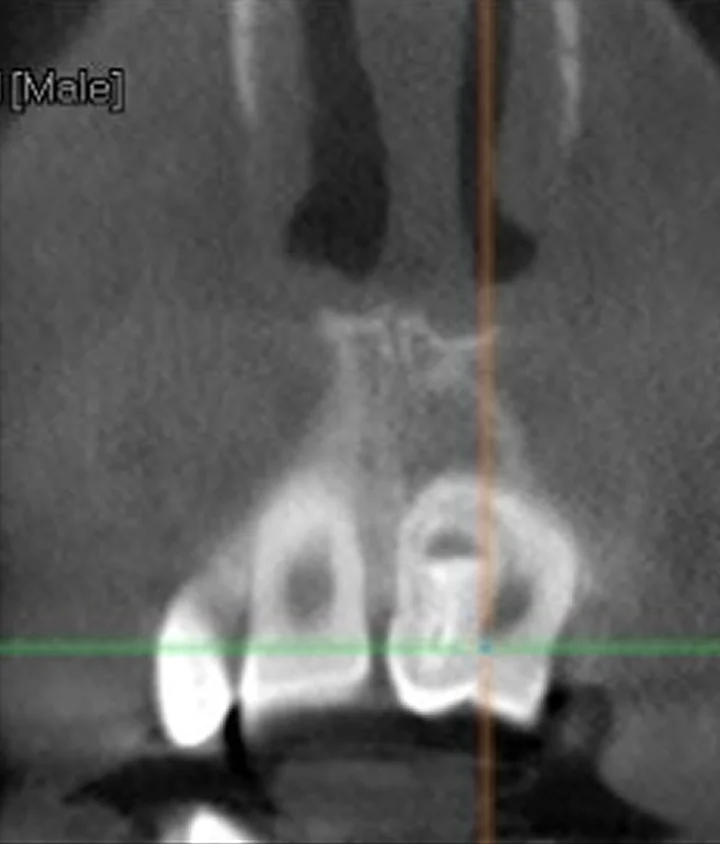

Зуб в зубе (dens invaginatus): диагностика и тактика лечения

Механизм формирования инвагинации. Клинические проявления и рентгенологическая картина. Риски осложнений и алгоритм принятия решения о лечении. Особенности эндодонтического лечения при разных степенях инвагинации.

Диагностировать dens invaginatus и выбрать тактику эндодонтического лечения в зависимости от степени инвагинации.

Классифицировать случай и принять обоснованное клиническое решение до начала лечения.